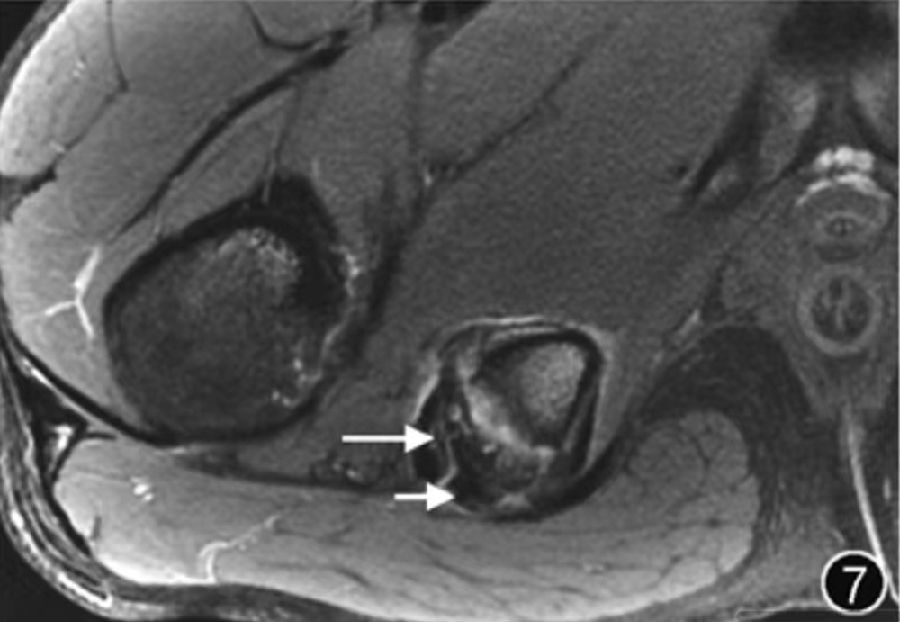

6.肌肉肌腱损伤:肌肉拉伤在所有急性运动损伤中占有较高比例,臀小肌、臀中肌肌腱是最常受损伤的臀部肌腱,大多撕裂是止点处的撕裂,部分撕裂比完全撕裂更常见。推荐进行MRI以更好地了解病变部位及范围、预测恢复时间及临床结局等相关信息。既往急性肌肉损伤通常分为拉伤(Ⅰ级)、部分撕裂(Ⅱ级)和完全撕裂(Ⅲ级)。尽管目前已有多种肌肉损伤分级和分类系统,如BAMIC 分类,可用于对损伤进行分级,但其临床应用价值有待明确(图7)。

图7 腘绳肌腱损伤MRI图像。

在坐骨结节层面的横断面T2WI中,可观察到走行在前外侧的半膜肌肌腱(长↑)及走行于坐骨结节外侧的股二头肌‑半腱肌联合肌腱(短↑)均增粗伴高信号